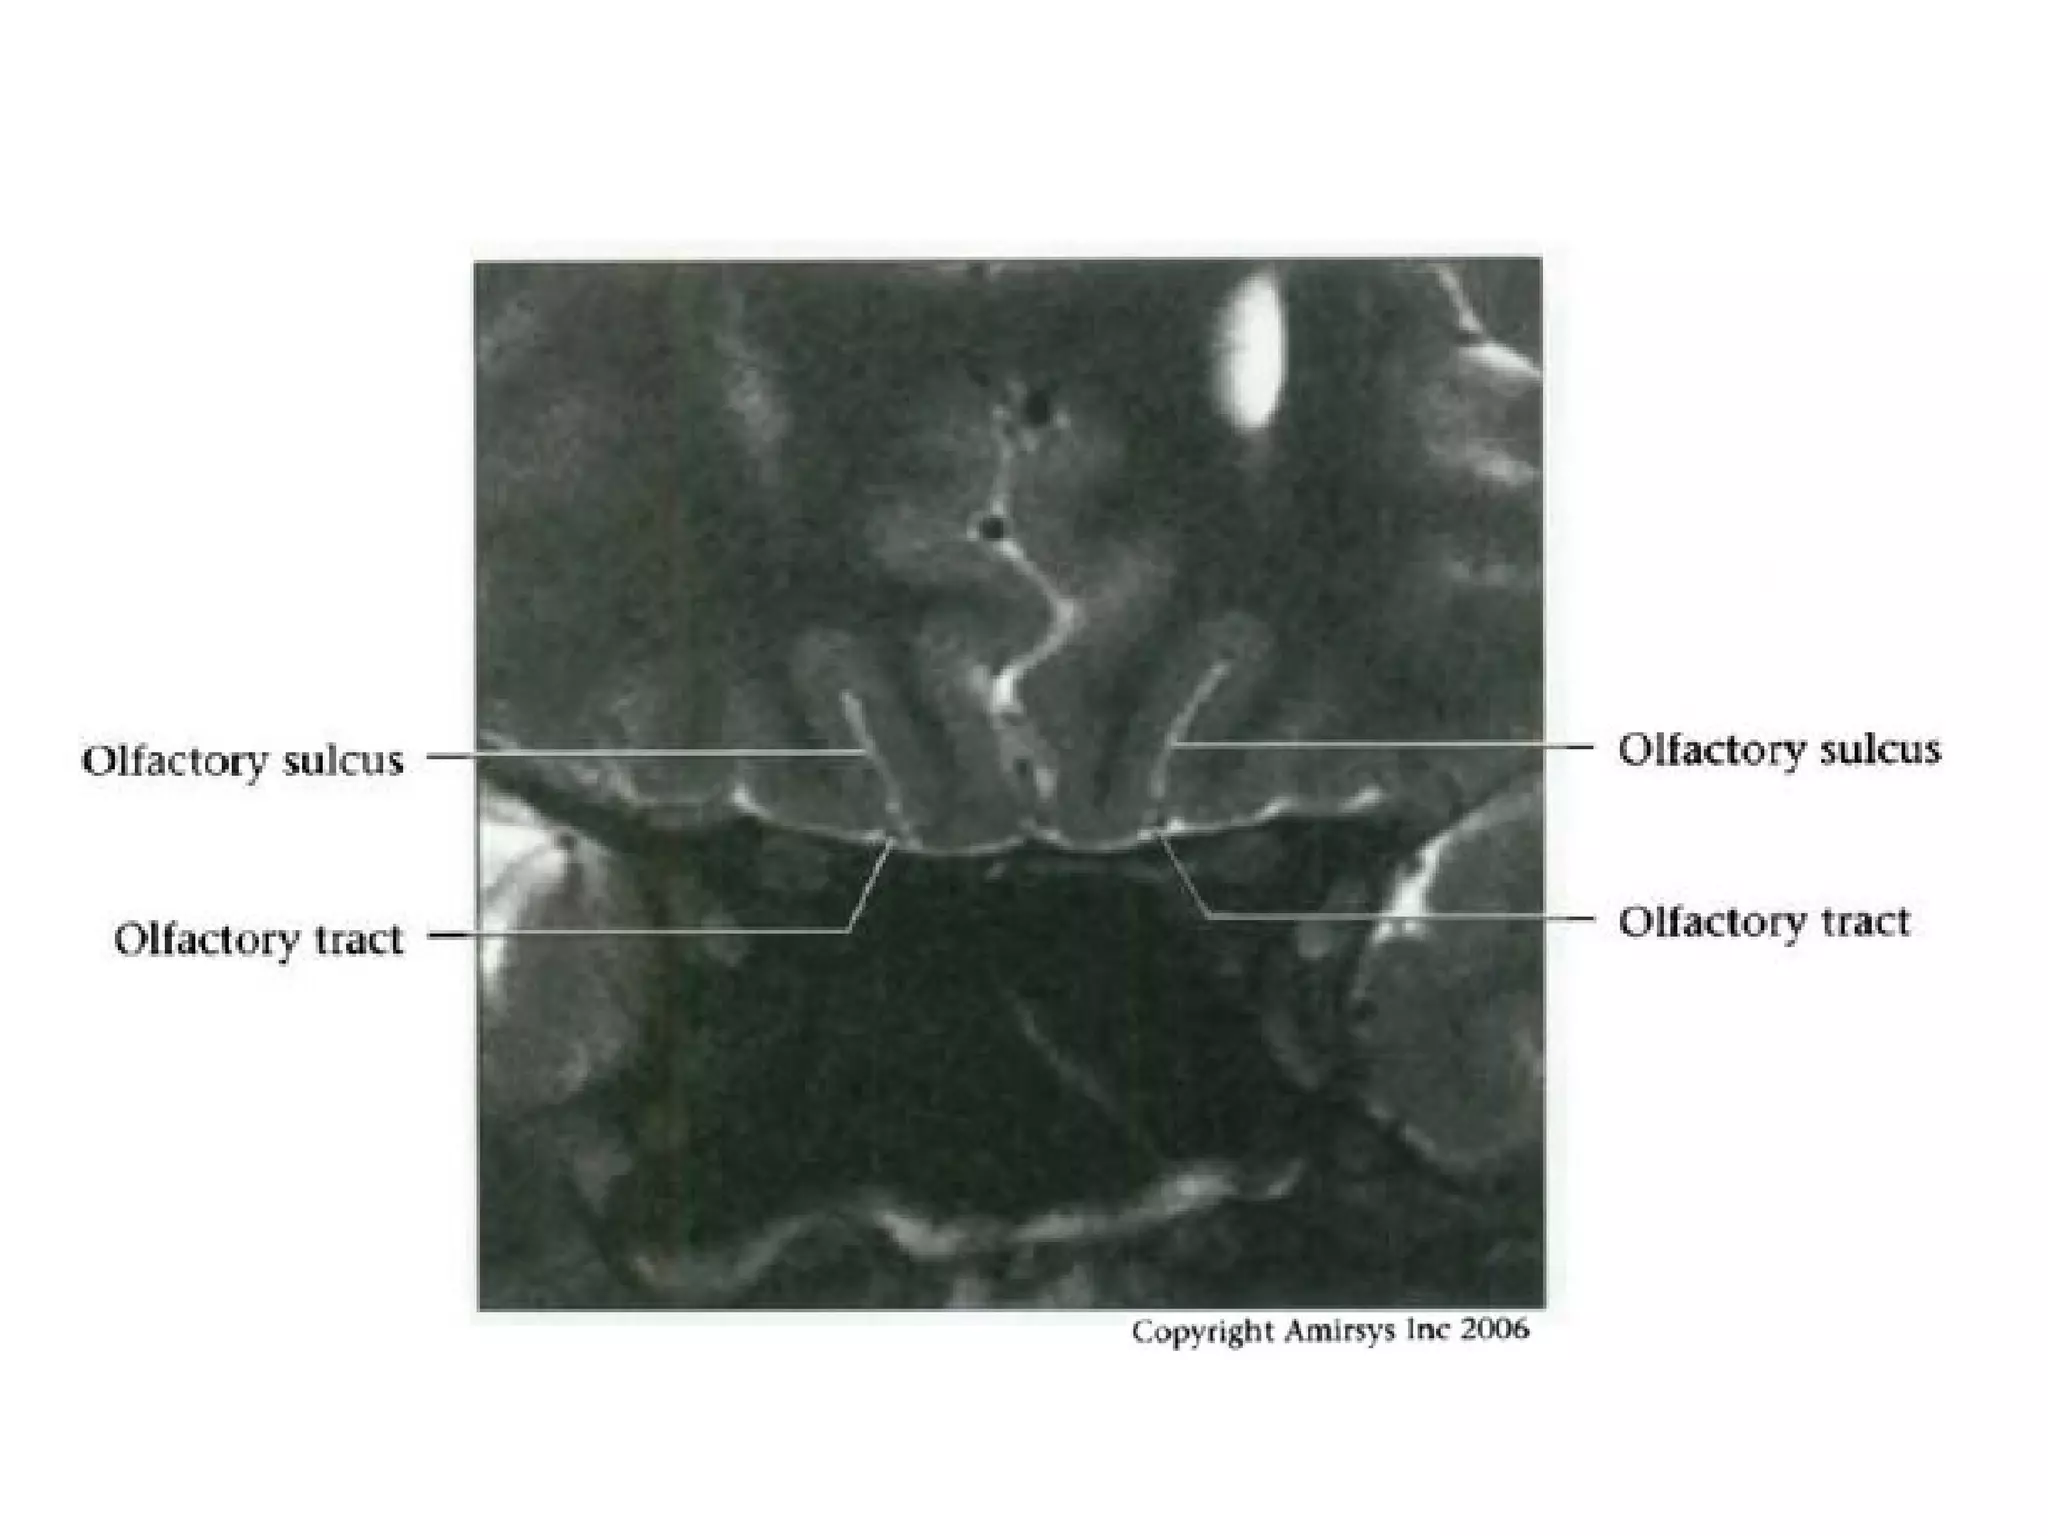

Cranial Nerve I:

The Olfactory Nerve

• These secondary axons in the olfactory nerve

eventually terminate in the inferomedial temporal

lobe, uncus and entorhinal cortex

• To avoid confusing the olfactory nerve with the

gyrus rectus on axial images, it is important to

remember that the olfactory nerve is situated

deep in the olfactory groove, inferior to the gyrus

rectus

• Coronal images are easiest to interpret because

the nerves are seen in cross section

RadioGraphics 2009; 29:1045–1055

Olfactory nerve.

Axial and coronal 0.8-mm-thick SSFP MR images show the olfactory nerve (white arrow)

within the CSF-filled olfactory groove and the optic nerve (black arrow) ringed by

highsignal-intensity CSF within the dural sheath.

Coronal 1.0-mm-thick SSFP MR image shows the cisternal segment of the olfactory

nerve (arrow), which is located inferior to and between the gyrus rectus (r) and the

medialorbital gyrus (o).